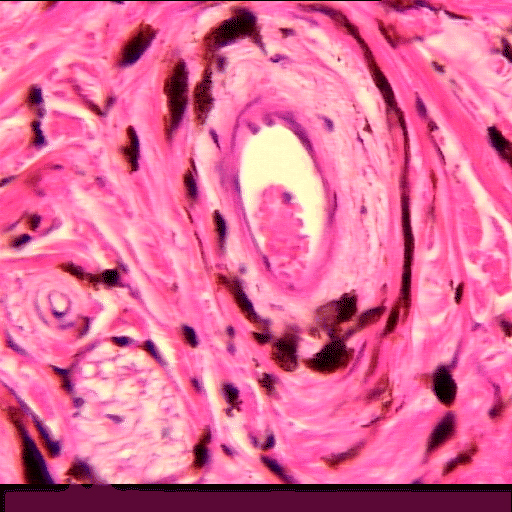

(EN) : Close-up view of a longitudinal section of the iris from an ox (Hematoxylin and eosin stain (H&E), x10, Slide RCB-45 P3.2).

(FR) : Vue rapprochée d'une coupe longitudinale de l'iris d'un bœuf (coloration à l'hématoxyline et à l'éosine (H&E), x10, Lame RBC-45 P3.2).